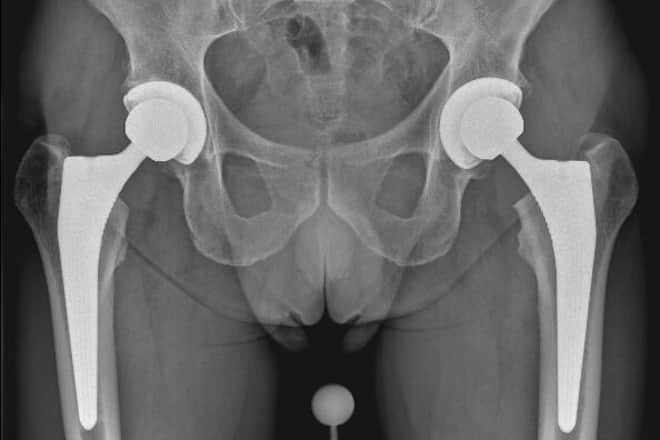

Zum andern ist das Material besser geworden. «Das Prinzip der Titanlegierung im Knochen des Oberschenkels und im Becken ist seit den 90er-Jahren gleich geblieben», sagt Munzinger. Der Kopf der Prothese besteht meist aus Keramik oder Metall. Der ganz grosse Change-Maker ist das hochvernetzte Polyethylen, das die Pfanne auskleidet. «Das ist Top-Qualität. Es entsteht viel weniger Abrieb, auch wenn das Gelenk stark belastet wird», gibt Hersche zu bedenken. Das Problem beim alten Polyethylen war, dass sich Abriebpartikel zwischen Knochen und Prothese hineingearbeitet haben. Das führte zu einer Lockerung der Prothese. «In der Literatur haben wir Studiendaten, die zeigen, dass mit dem hochvernetzten Polyethylen grössere Köpfe verwendet werden können als mit dem alten Material. Je grösser der Kopf, desto weniger Luxationen», sagt PD Dr. Stefan Rahm. Klare Regeln, ob Kurz- oder Standardschaft, gibt es nicht. Der kurze Schaft ist zeitgleich mit der Einführung des vorderen Zugangs aufgekommen. «Aufgrund der Exposition des Oberschenkelknochens kann er einfacher implantiert werden.» Als viel wichtiger erachtet Hersche die zuverlässige Ver-ankerung der neuen Schäfte. Dadurch ist das Gelenk sofort belastbar. Komplett mit dem Knochen verwachsen ist der Schaft in zwei bis drei Monaten.